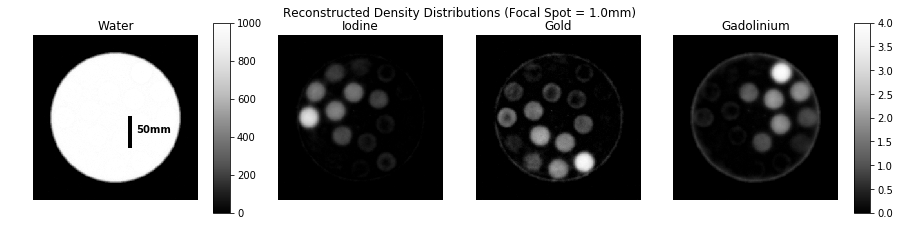

Refer to caption

Figure 5: Example of a material decomposition result for a focal spot width of 1.0mm.

The geometry and sampling conditions for the studies are summarized in Table 1. A digital phantom (Figure 3) of a 100 mm diameter water cylinder and several 15mm diameter cylindrical inserts containing various mixtures of iodine, gold, and gadolinium was employed. The outer ring includes single-contrast inserts of 0.5-4.0 mg/mL concentrations. The inner ring includes mixtures of 1.0 mg/mL and 2.0 mg/mL for all combinations of two materials. The center of the phantom also includes 10.0 mg/mL single voxel impulses of each material for regularization tuning.

Figure 3: Ground truth of the numerical phantom. Magenta text indicates the density in mg/mL of iodine, gold, or gadolinium (corresponding to image subtitle) in cylindrical inserts.

In the imaging results for the focal spot experiment, the 0.2 mm and 1.0 mm focal spot width cases are very difficult to distinguish by eye. Overall the reconstructed densities are a reasonable approximation of the ground truth. The low-contrast 0.5 mg/mL insert is visible in both cases which implies that the spatial-spectral filter has the potential to improve sensitivity to lower concentrations. A focal spot size of 1.0mm is fairly standard, so the material decomposition appears to be effective in the presence of realistic focal spot blur effects.

For focal spot widths between 0.2-1.0 mm, the final RMSE values were less than 0.35 mg/mL for each material. In the case of gadolinium, the RMSE was less than 0.18 mg/mL for this range. Larger-than-average focal spot widths such as 2.0 mm and 4.0 mm resulted in RMSE values around 0.47 mg/mL. The overall trend shows that larger focal spot widths lead to greater error. However, the change in RMSE is less than 15% between the 0.2 mm and 1.0 mm cases for any individual contrast agent so the impact is not severe. One notable error is the insert containing 4.0 mg/mL of iodine on the left side of the image. The reconstructed density of iodine is underestimated at 2.75 mg/mL and around 1.25 mg/mL is erroneously attributed to gold. This could indicate that for the given combination of filter materials, iodine and gold are particularly difficult to distinguish. This issue may also be improved with a more sophisticated regularization scheme, more spectral channels, or higher fluence.